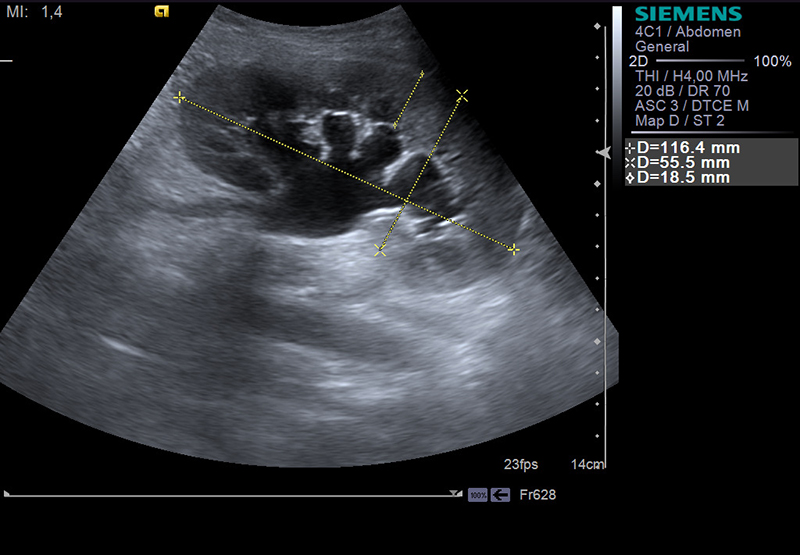

- УЗИ почек с эффектом контрастной подсветки (допплерометрии);

При подозрении на воспаление почек пациент направляется на комплексное обследование. Обязательным является анализ мочи по различным параметрам, общий и биохимический анализ крови. Уточнить состояние почек позволяет ультразвуковое и радиоизотопное исследование, а также биопсия тканей в предположительной области воспаления. Основная цель диагностических мероприятий — выявить причины и пути распространения инфекции внутри организма.